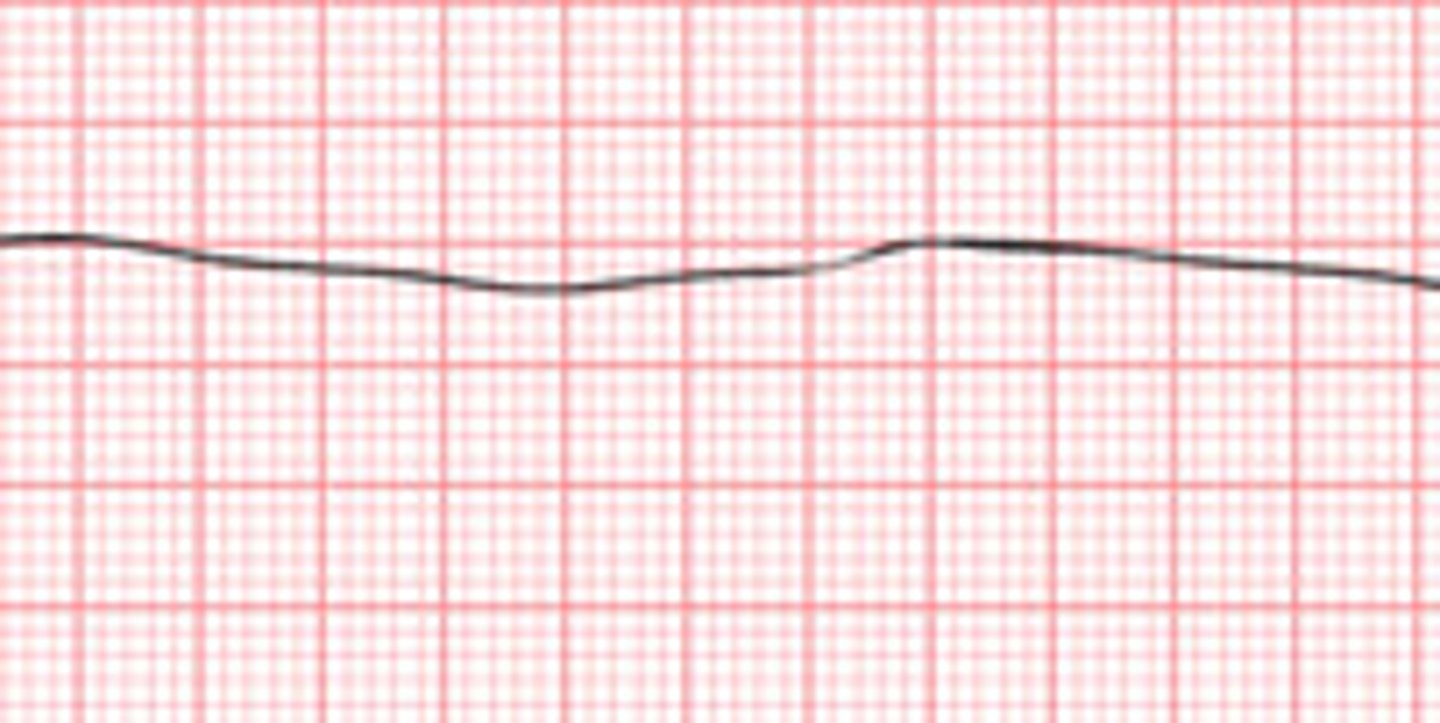

What is asystole?

flat line, no QRS present, no pulse, HR=0, no BP, lethal if not corrected in 3-5 minutes.

What is the treatment for asystole?

DO NOT SHOCK!!!!! CPR, check asystole in two leads, epinephrine, pacemaker, consider the causes.